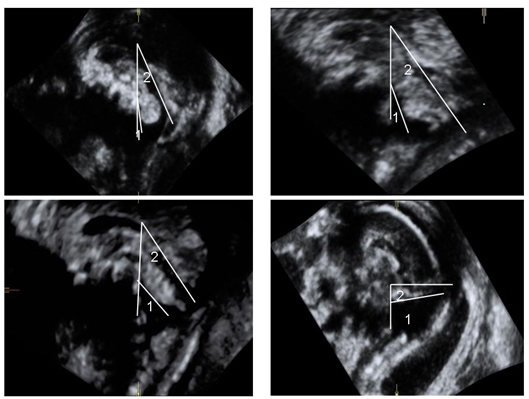

选择同期超声诊断为小脑蚓部发育异常并经胎儿磁共振成像证实与超声诊断相符的胎儿16例(小脑蚓部异常组)。16例小脑蚓部发育异常胎儿中4例Dandy-Walker畸形胎儿小脑蚓部受压明显上抬,BV角测值明显增大为62.7~104.5°,平均为(88.9±18.1°),小脑幕上抬,BT角测值明显增大为74.3~103.4°,平均为(89.0±12.8°);6例Dandy-Walker变异胎儿小脑蚓部上旋,BV角测值增大为18.4~31.1°,平均为(23.7±5.2°),BT角测值稍增大为42.9~71.7°,平均为(54.5±12.0°);6例Blake囊肿胎儿小脑蚓部上旋,BV角测值轻度增大为13.9~18.5°,平均为(16.7±1.8°),BT角测值为42.7~61.2°,平均为(50.3±8.2°)。

胎儿小脑蚓部正中矢状切面BV角和BT角的测量可直观显示小脑蚓部发育异常组胎儿小脑蚓部上旋和小脑幕上抬的程度。Blake囊肿、Dandy-Walker变异、Dandy-Walker畸形3类病例中的BV角均大于正常组胎儿的BV角,且随着小脑蚓部发育异常程度的增加而增加。Dandy-Walker畸形胎儿的BV角>60.0°,Blake 囊肿中BV角>10.0°但<20.0°,Dandy-Walker变异胎儿的BV角位于中间。BV角的定量测量在一定程度上可对伴有蚓部上旋的蚓部发育异常的病例进行鉴别诊断。BT角在小脑蚓部异常组胎儿中也会增大,尤其在Dandy-Walker畸形病例中,小脑幕受压明显上抬,BT角明显增大。但在其他2类疾病中,BT角的测量值会有重叠,限制了其在这2组疾病中的鉴别诊断价值。

注:1为BV角,2为BT角

图5 Blake囊肿胎儿BV角、BT角的测量,显示测量值分别为18.5°、43.0°

图6 Dandy-Walker变异胎儿BV角、BT角的测量,显示测量值分别为28.7°、46.1°

图7 Dandy-Walker畸形胎儿BV角、BT角的测量,显示测量值分别为94.5°、103.4°